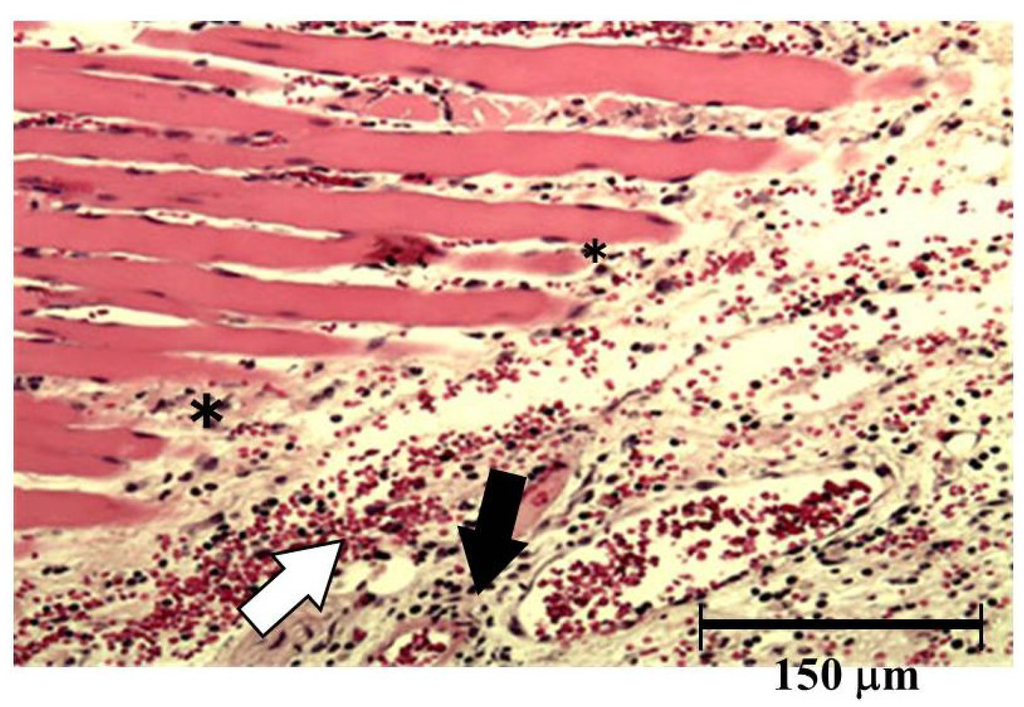

Both hemorrhage and permeation of neutrophil to the tissue were observed after injection of okinalysin into mice thigh (Figure 6). Destruction of muscular fiber also occurred 24 h after injection. However, these phenomena were relatively mild compared to metalloproteinases in other viperidae venoms such as P. flavoviridis and Gloydius blomhoffii, which possess strong hemorrhagic activity with a dose of 0.01–0.1 μg/mouse.

Figure 6. Light micrograph of muscle from the thigh of mice. Okinalysin (0.17 mg) was intramuscularly injected. White arrow: the emigration of red blood cells; Black arrow: neutrophil infiltrations; *: destruction of muscular fiber.